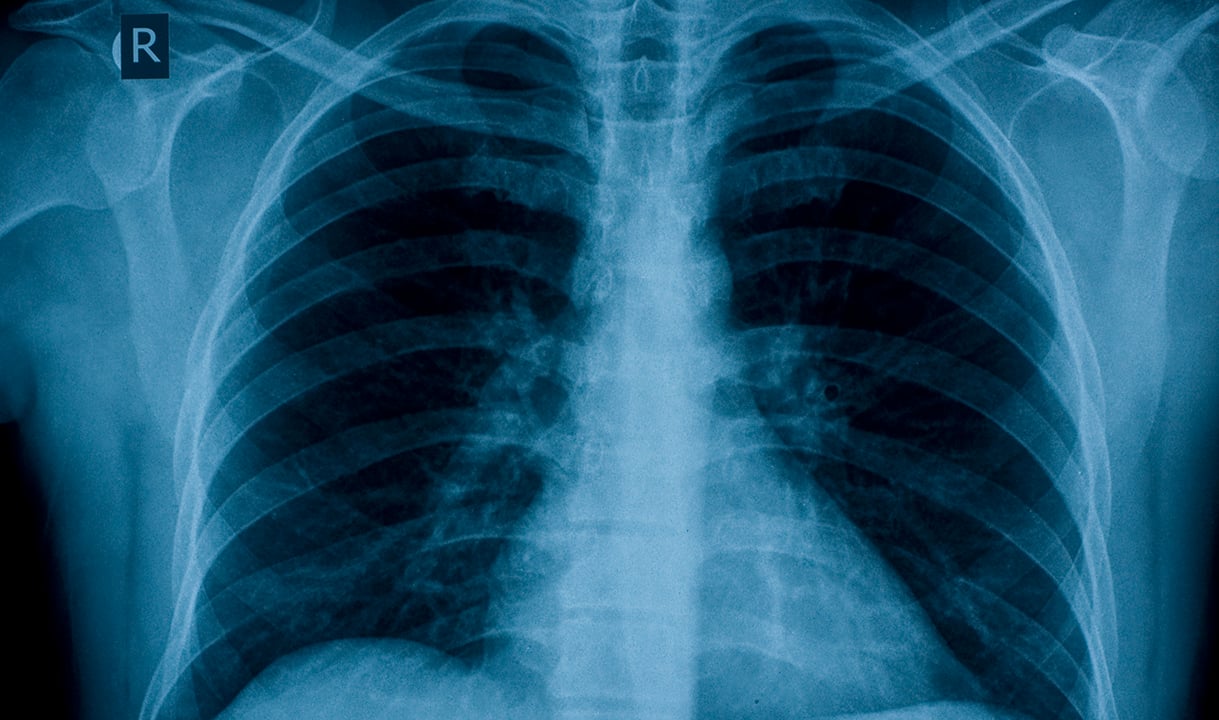

The bacteria in your mouth do not just stay there; you may accidentally inhale them into your lungs through saliva droplets without even noticing! This may not be an issue for those with healthy lungs, but people with existing lung problems or those who are more vulnerable could end up with infections like pneumonia or chronic obstructive pulmonary disease.

Chronic obstructive pulmonary disease (COPD), a progressive, lifelong lung disease that affects over 250 million people worldwide, has also been linked to poor oral health. COPD not only makes it harder to breathe, it also puts you at higher risk of developing other health conditions like heart disease and lung cancer.